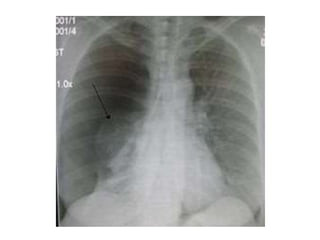

RADIOGRAPHICDIAGNOSIS

1- CXR

The standard procedure in making the diagnosis.

 It should be upright and preferably in the posteroanterior

projection. It is possible to miss a pneumothorax in a

semisupine portable anteroposterior view. If the patient

cannot be upright, a lateral decubitus view with the suspect

side positioned up may be helpful.

 A giant bulla can mimic a pneumothorax. Subtle lines demarcate

a bulla, which tends to be surrounded by thickened visceral pleura.

In addition, a pleural line can frequently be seen with lung

markings visible beyond the suspected bulla (double wall sign)